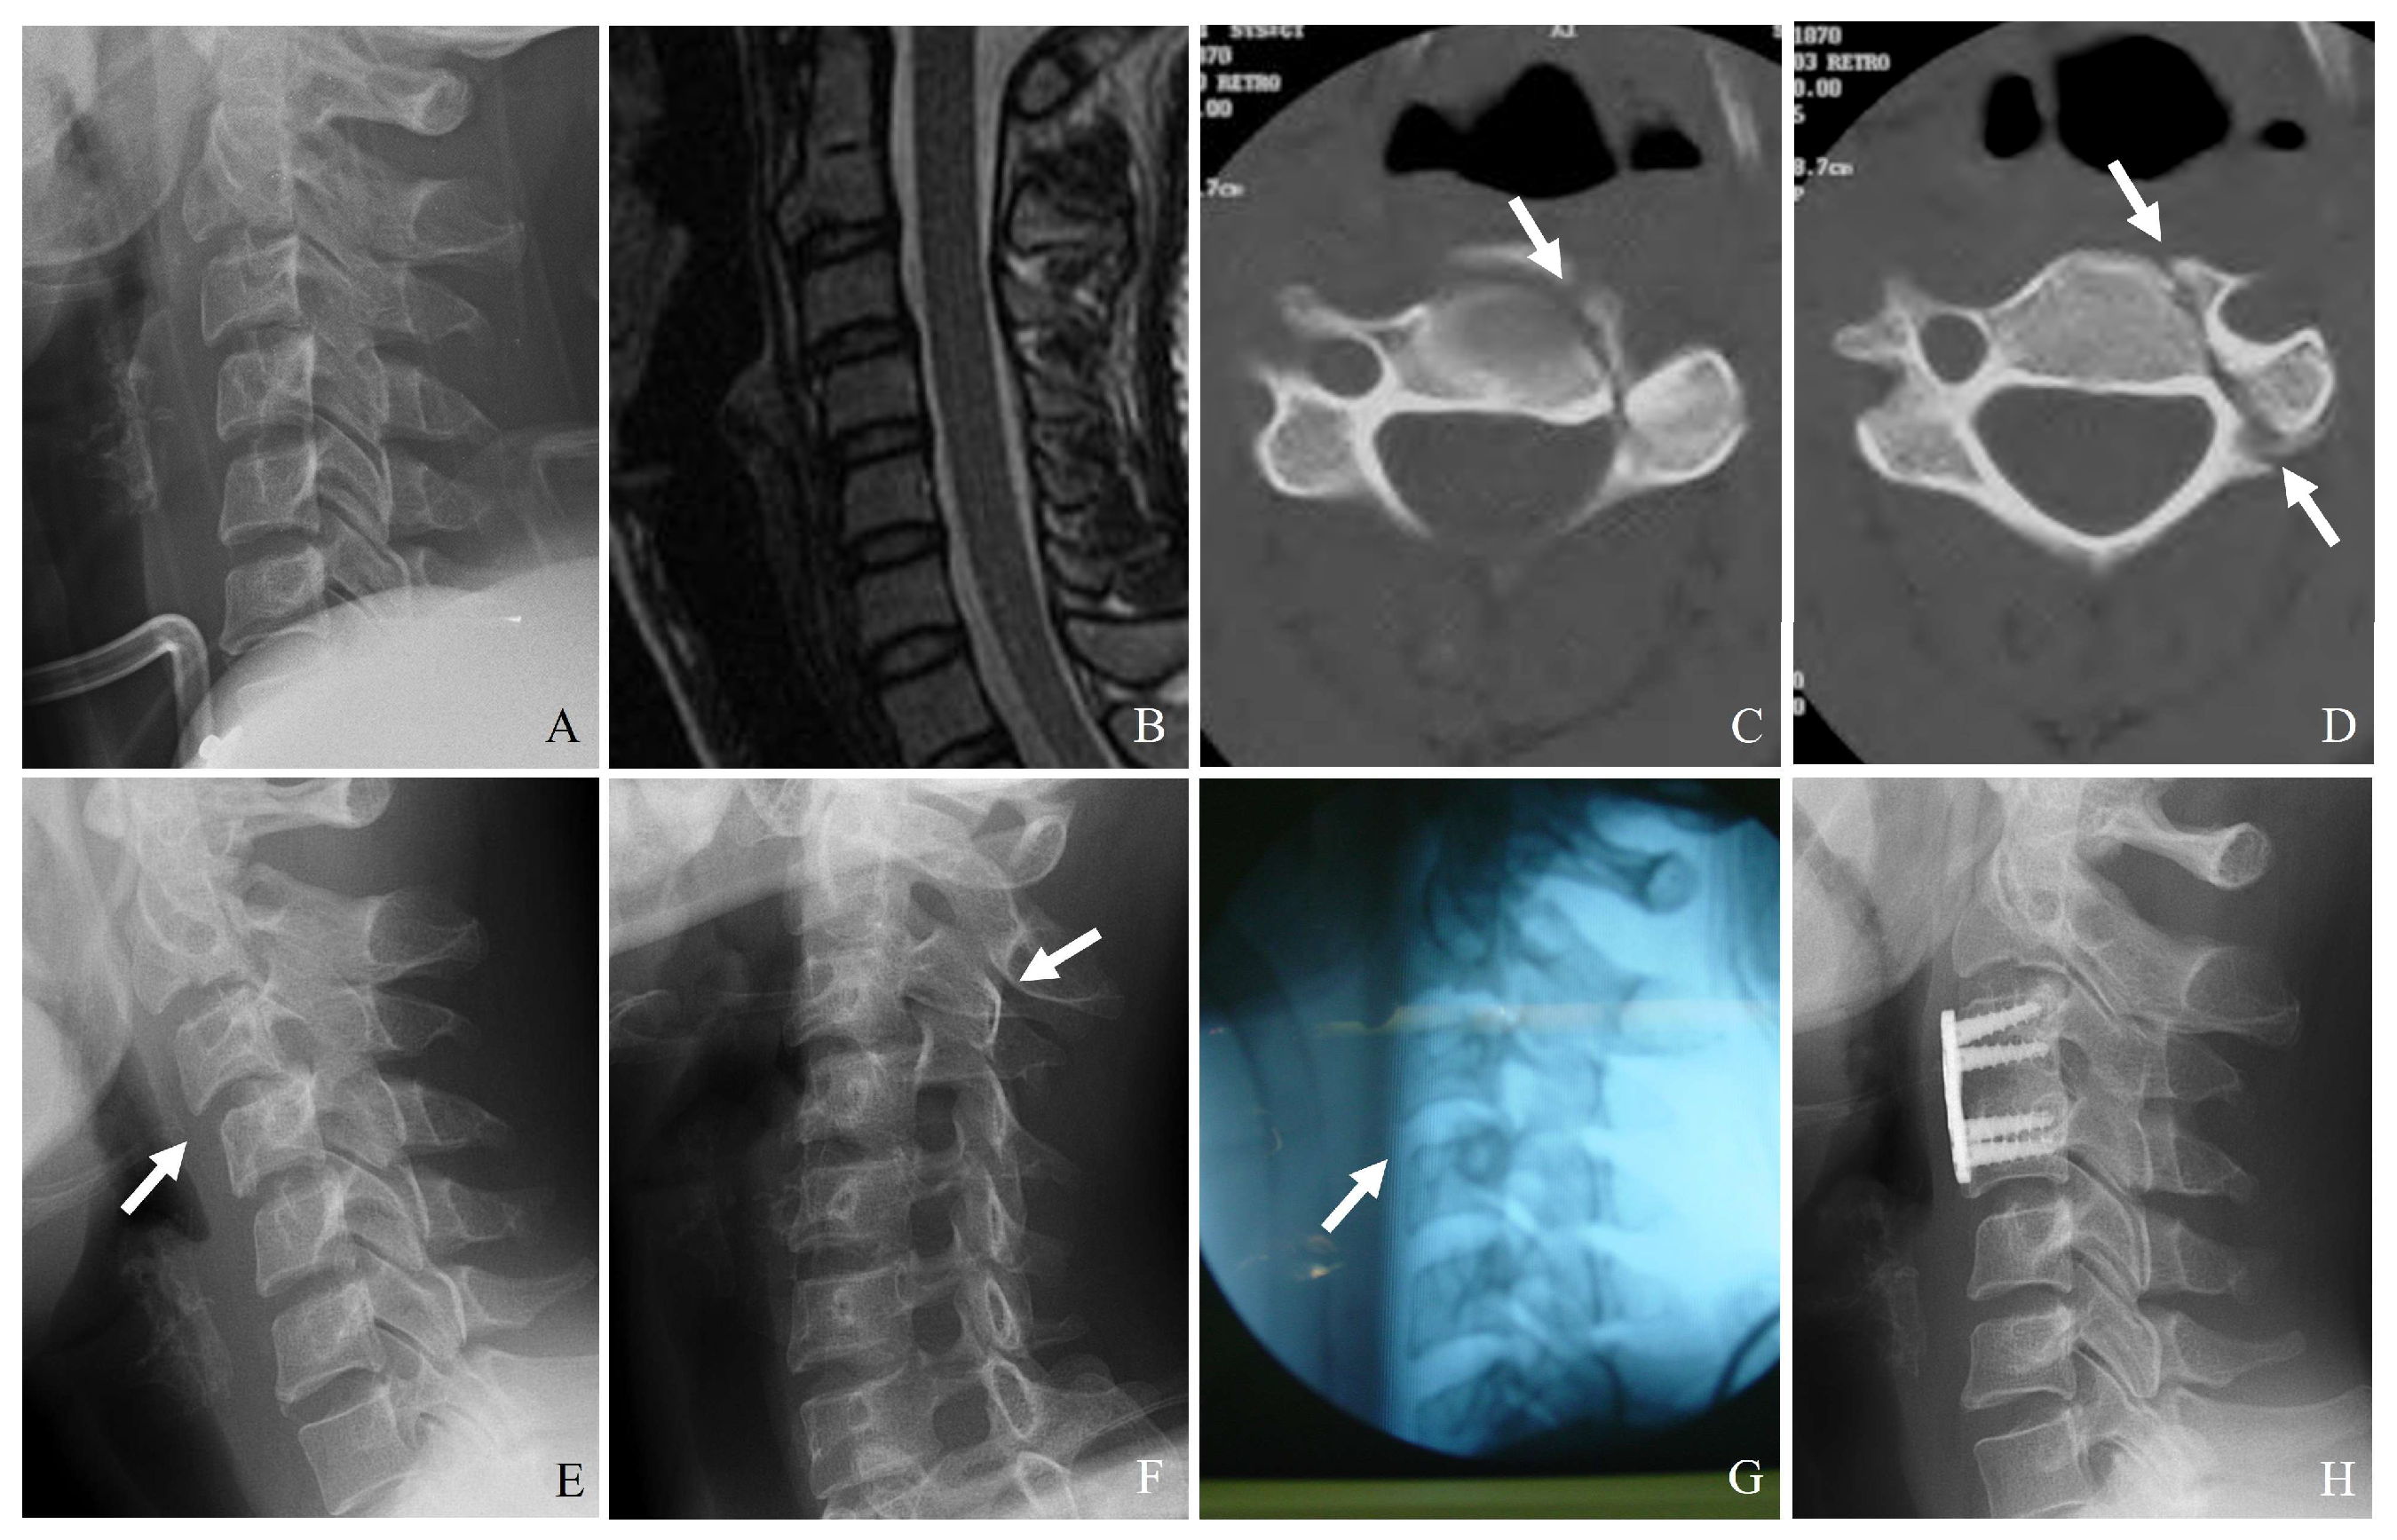

3.1. Plain Radiography

3.2. Computed Tomography (CT)

3.3. Magnetic Resonance Imaging (MRI)

- Fracture of the lateral mass or pedicle can lead to direct bony impingement on the vertebral artery (Figure 8).

- CT angiography: The gold standard for detecting vertebral artery injuries (Figure 9).